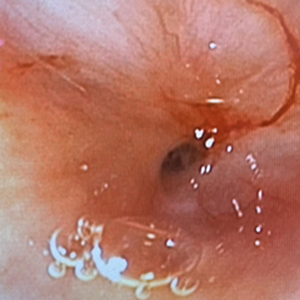

気管の内視鏡検査

スワブ生検

気管虚脱に加え、スワブ検査で炎症が見られました。

培養と細胞診の結果によるお薬の使用で、現在は比較的良好にコントロール出来ています。